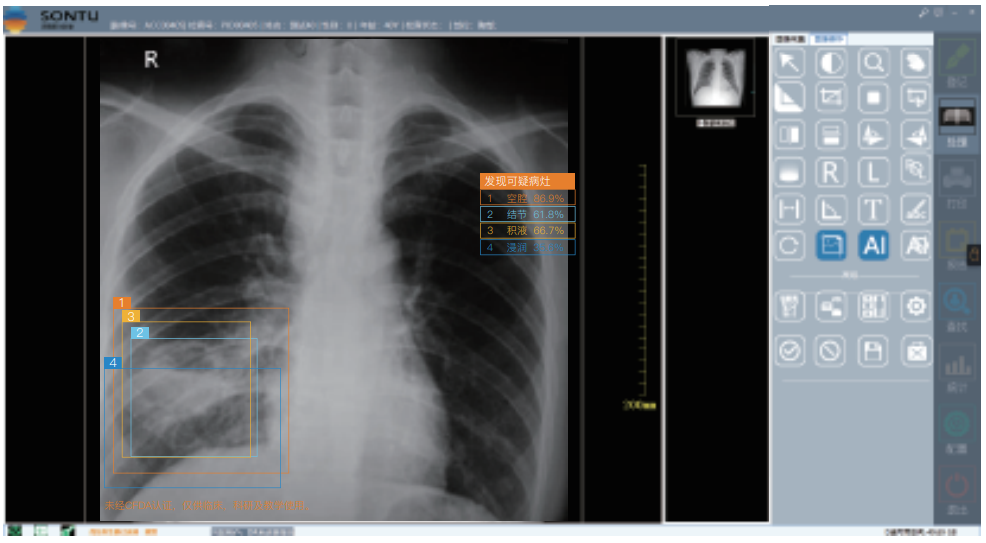

深图软件操作系统:

一键即可完成辅助诊断,定位可疑病变

深图AI辅助诊断系统标注示意:

标注异常位置、呈现病变信息